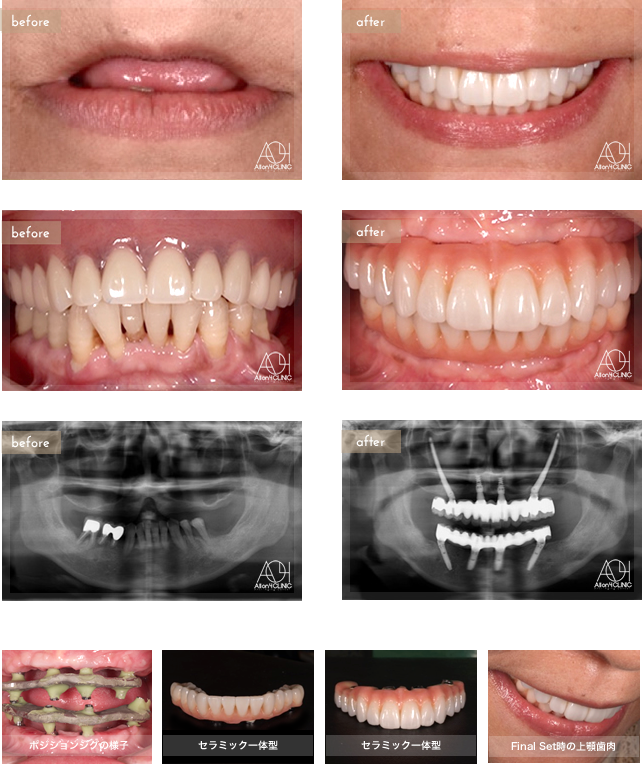

Age : 67

Sex : female

Treatment : 2013

-Maxilla Zygoma Hybrid

- Under All-on-4

Age : 61

Treatment :

- Maxilla All-on-4

上顎は両側Zygoma、前方Nobel Active2本埋入。下顎Speedy Groovyインプラントを4本埋入。上顎はセラミック一体型、下は基 底面セラミック人工歯タイプ。